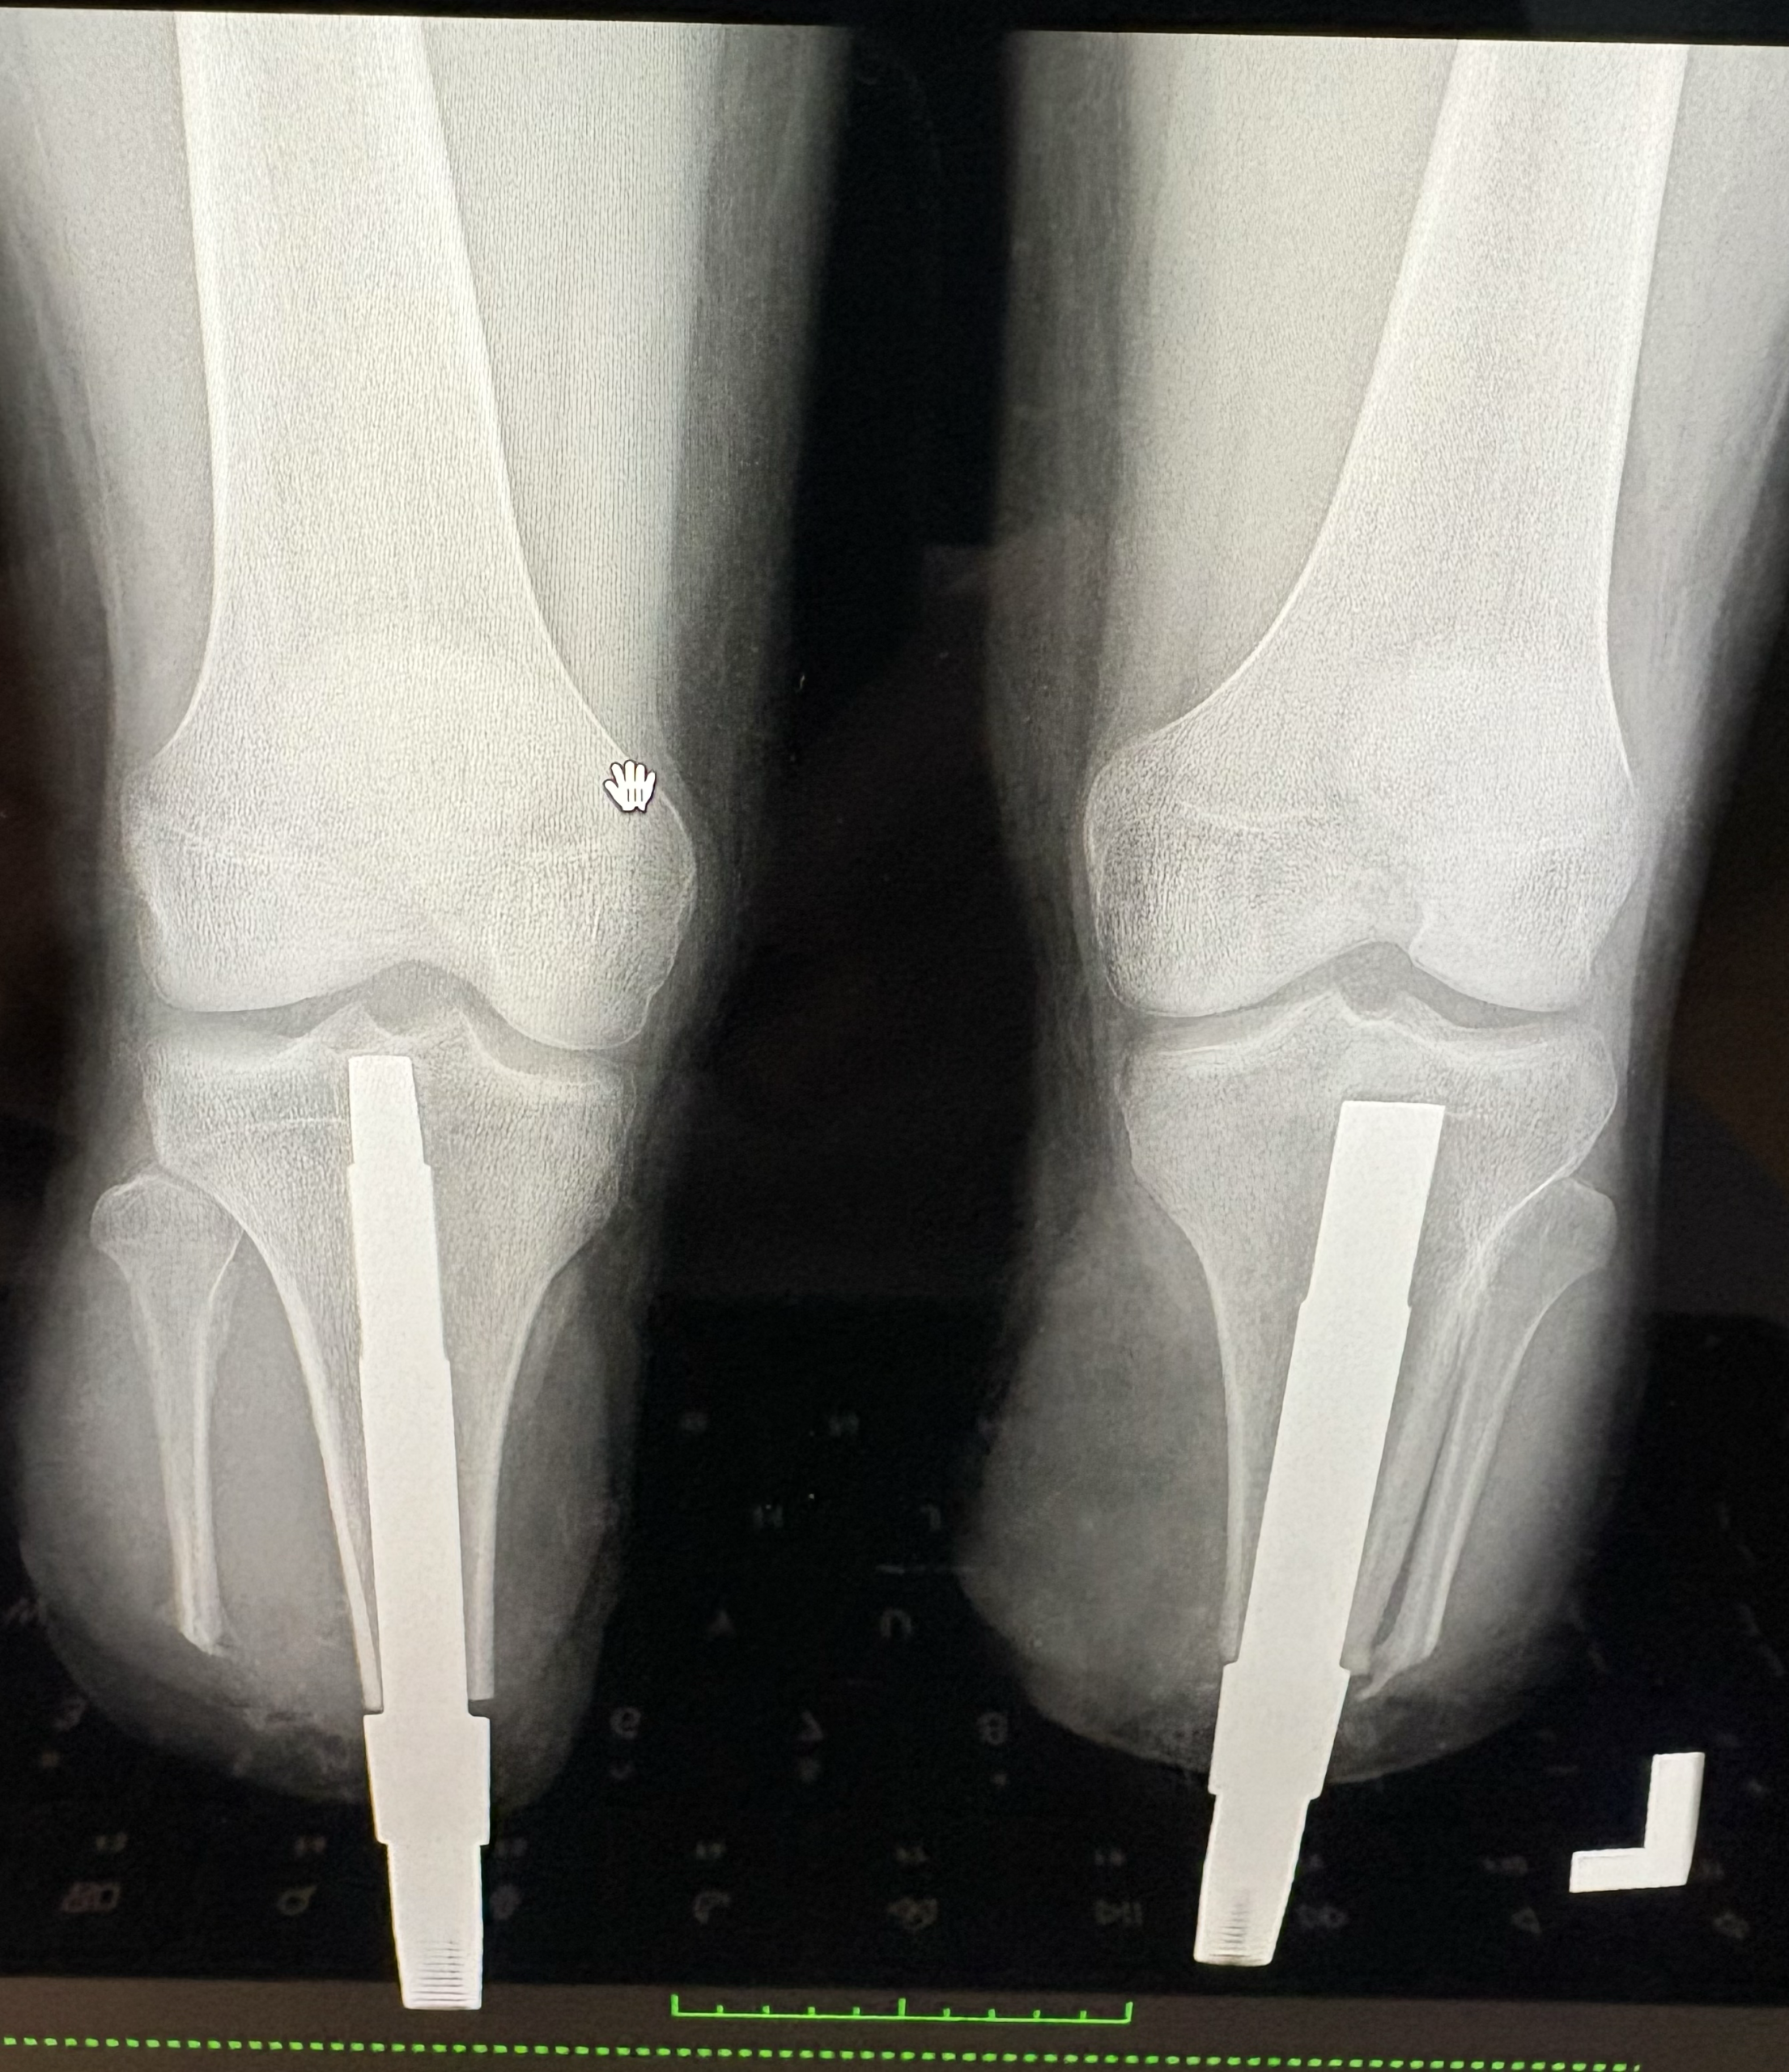

W Klinice Traumatologii i Ortopedii WIM-PIB przeprowadzono innowacyjny i rzadko wykonywany zabieg jednoczasowej osseointegracji obu podudzi u 19-letniego pacjenta po amputacji urazowej. To ważny krok naprzód w nowoczesnym leczeniu osób po amputacjach kończyn dolnych.

Osseointegracja polega na trwałym połączeniu implantu z kością, co umożliwia bezpośrednie mocowanie protezy bez konieczności stosowania tradycyjnego leja protezowego. Rozwiązanie to zapewnia pacjentom większy komfort użytkowania, lepszą kontrolę ruchu oraz wyraźną poprawę jakości życia. Przeprowadzona operacja była szczególnie wymagająca, ponieważ objęła obie kończyny jednocześnie. Jednoczasowe wykonanie zabiegu niesie jednak istotne korzyści – pozwala uniknąć drugiej hospitalizacji i kolejnego znieczulenia ogólnego, skraca całkowity czas leczenia oraz umożliwia prowadzenie symetrycznej rehabilitacji obu kończyn już od początku procesu usprawniania. Dzięki temu pacjent ma szansę szybciej powrócić do samodzielnego funkcjonowania.